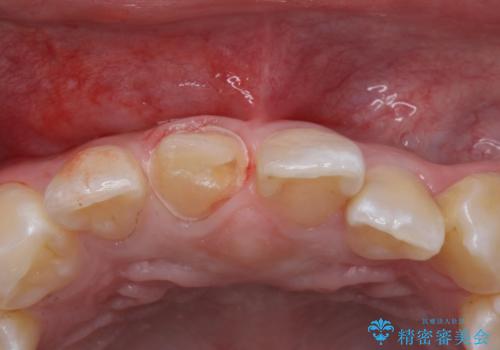

- 前歯のかぶせ物の色が気になるとのことで来院された患者様です。

セラミッククラウンで作り変えていきます。

- 右上1: 仮歯/11,000円、ジルコニアクラウン(スタンダード)/121,000円 合計132,000円(税込)費用は治療当時の料金となります